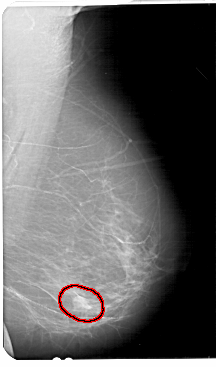

FILE: A_1681_1.RIGHT_CC.OVERLAY

TOTAL_ABNORMALITIES 1

ABNORMALITY 1

LESION_TYPE MASS SHAPE ROUND MARGINS ILL_DEFINED

ASSESSMENT 4

SUBTLETY 3

PATHOLOGY BENIGN

TOTAL_OUTLINES 1

BOUNDARY